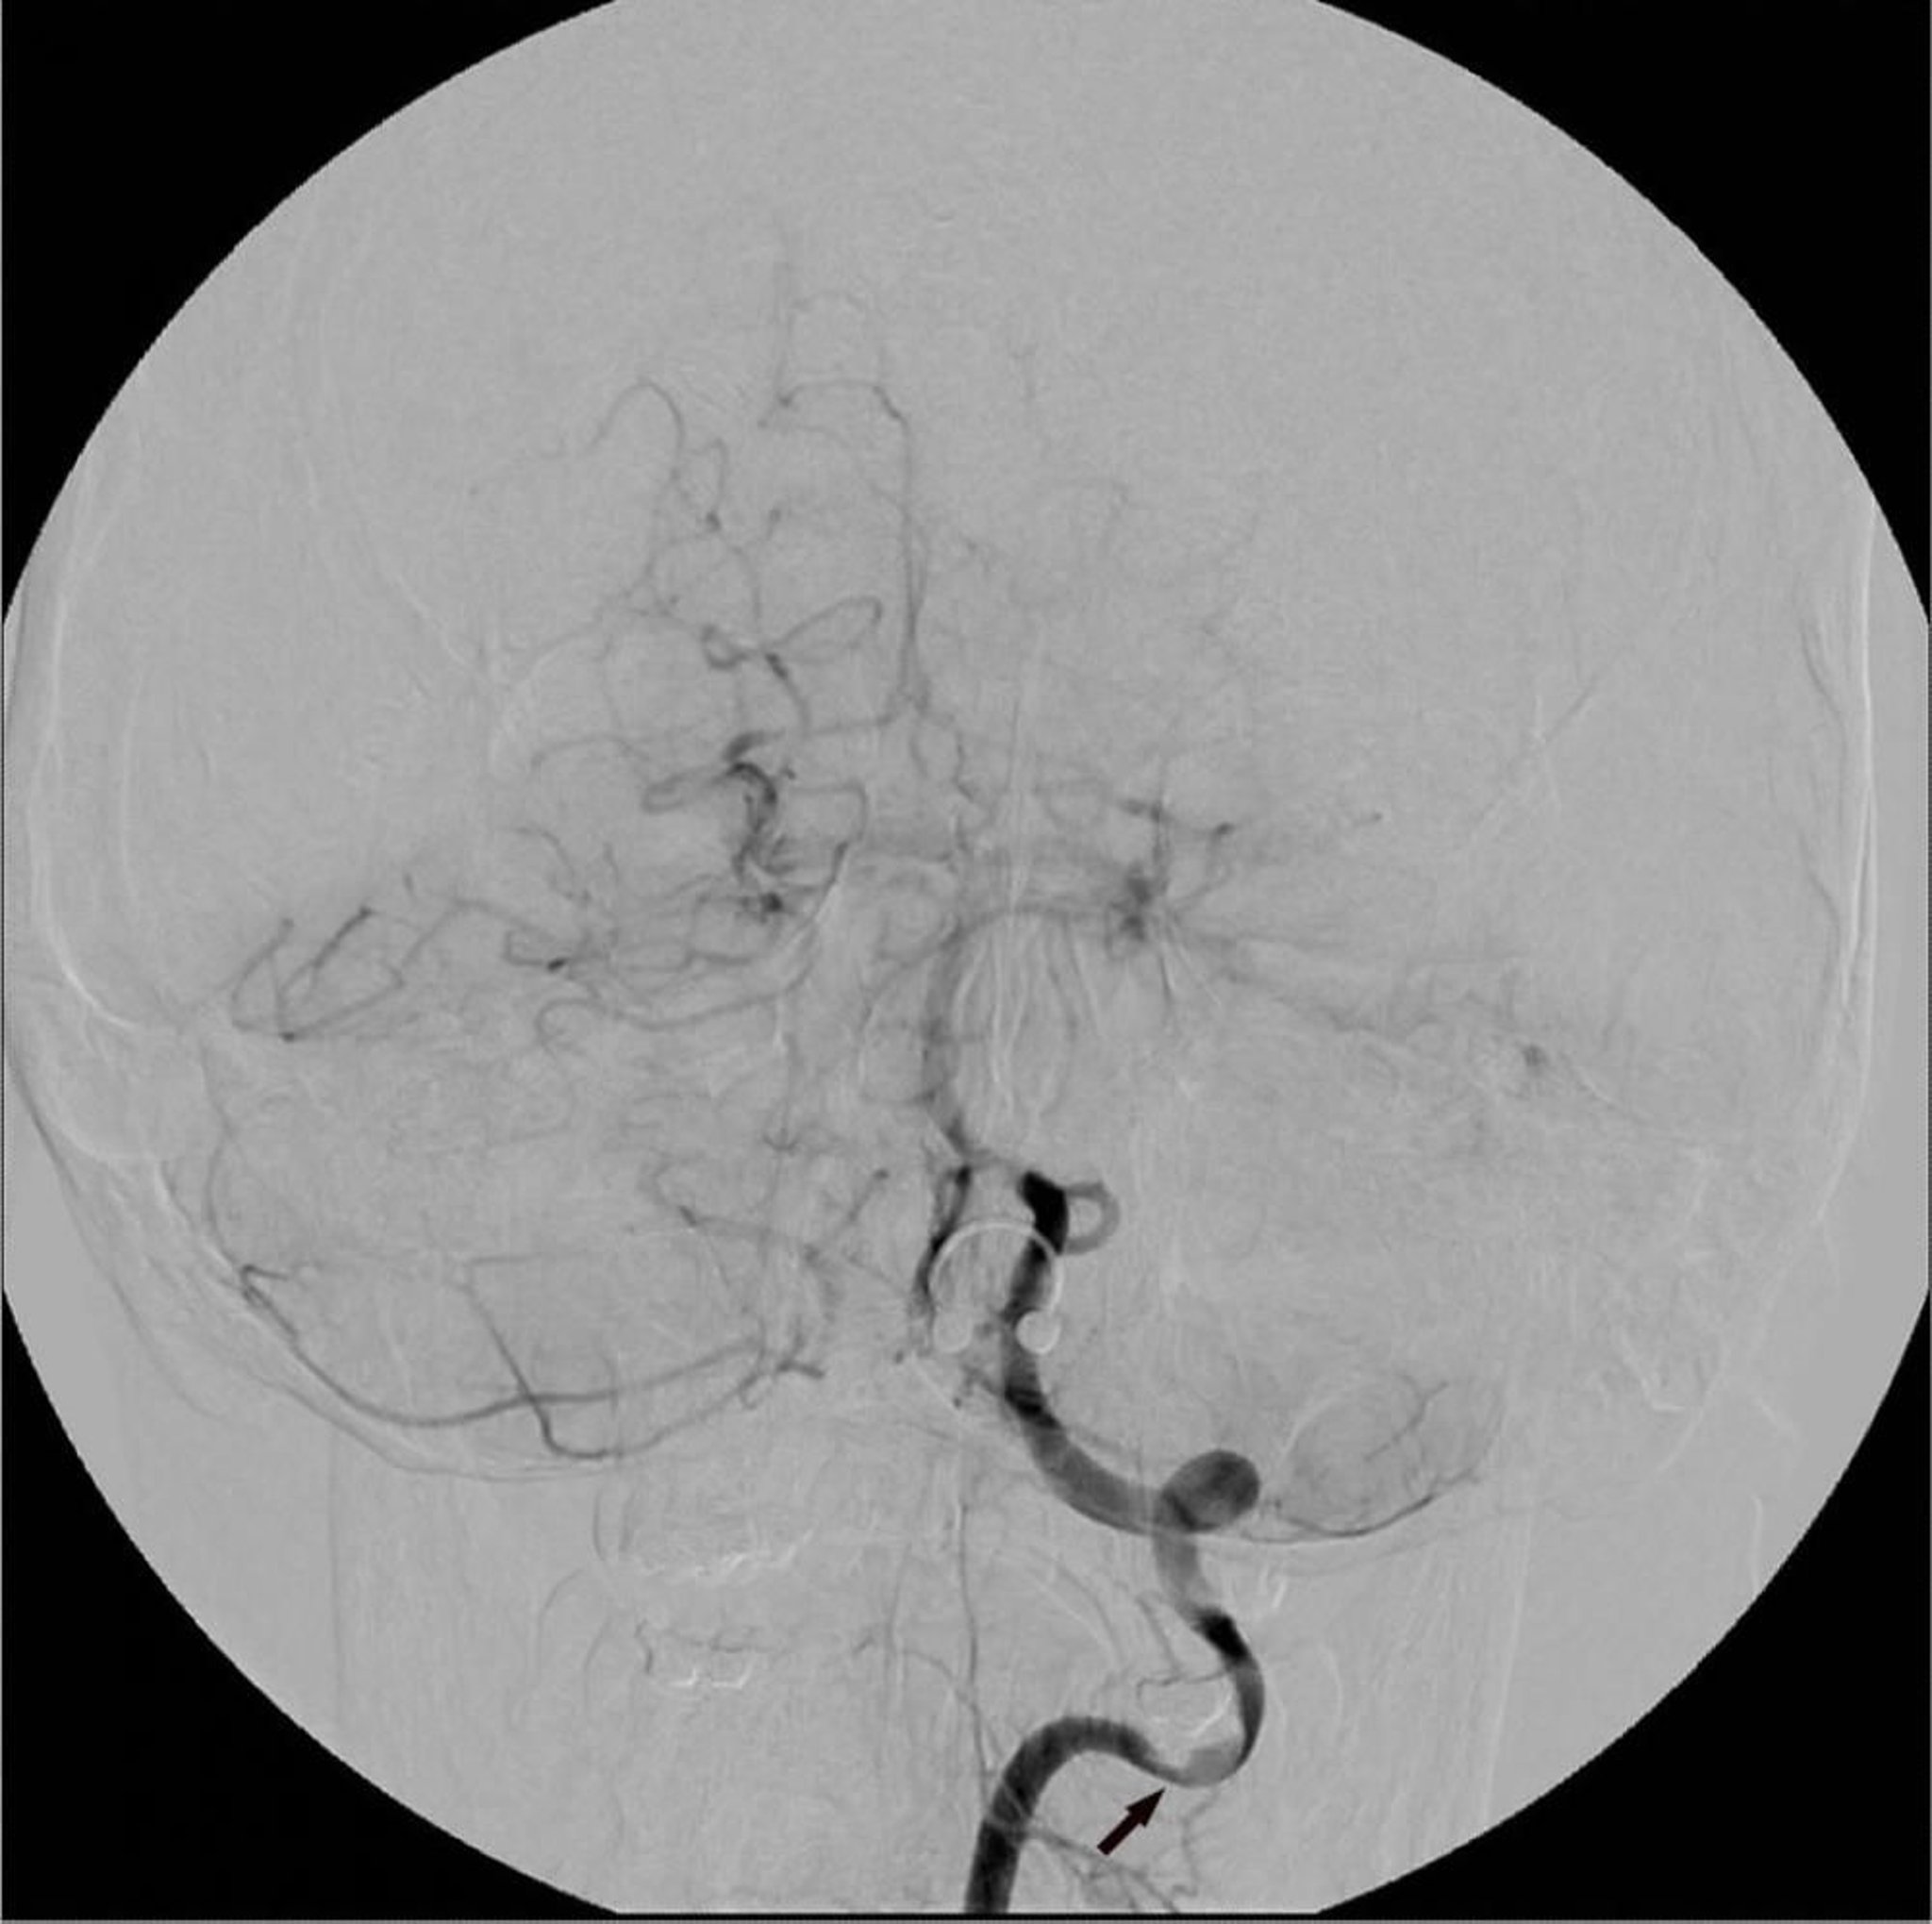

Angiography is sometimes called conventional angiography to distinguish it from CT angiography (CTA) and magnetic resonance angiography (MRA). Angiography provides detailed images of blood vessels, commonly those in the heart, lungs, brain, and legs. Angiography can provide still images or motion pictures (called cineangiography).

CTA and MRA are often done instead of conventional angiography. However, conventional angiography is the traditional gold standard for evaluating vascular lesions (eg, stenosis, obstruction, arteriovenous or other vascular malformations, aneurysms, dissections, vasculitis).

Images of blood vessels are taken before and after contrast injection; then a computer subtracts the pre-contrast image from the post-contrast image. Images of extraneous structures are thus eliminated, isolating images of the blood vessel lumens opacified by contrast.